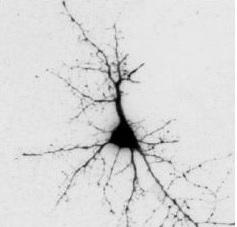

L'alpha-synucléine est une protéine normalement produite par les neurones du cerveau. Dans les maladies d'Alzheimer et de Parkinson, l'alpha-synucléine est agrégée sous une forme agglomérée appelée amyloïde, entraînant ces dommages aux neurones. Les chercheurs ont émis l'hypothèse que les protéines similaires produites par les bactéries du microbiote favorisent les anomalies de pliage des protéines du cerveau par un processus nommé « ensemencement croisé », ce qui conduit finalement à la formation d'agrégats de protéines cérébrales. Une autre hypothèse serait que les protéines amyloïdes produites par le microbiote amorcent l'activation de cellules immunitaires dans l'intestin, entraînant une inflammation accrue dans le cerveau.

La preuve par l'expérience : l'expérience a consisté à administrer des souches bactériennes E. coli -qui produisent la protéine bactérienne amyloïde- à des rats (groupe 1). Les animaux témoins (groupe 2) ont reçu des bactéries identiques mais qui ne présentaient pas cette capacité de produire la protéine amyloïde bactérienne. L'expérience montre que les rats du groupe 1 présentent une augmentation des niveaux de protéine alpha-synucléine dans les intestins et le cerveau, une augmentation des agrégats dans le cerveau et une inflammation cérébrale, vs les rats du groupe 2.

Cette nouvelle compréhension du rôle possible du microbiote dans la neurodégénérescence peut permettre de découvrir de nouveaux facteurs responsables du développement de ces maladies neurologiques, et finalement, de nouvelles approches préventives et thérapeutiques ciblant directement le microbiote. « Ces nouvelles données montrent que les protéines produites par les bactéries de l'intestin peuvent être facteur d'amorçage de la pathogenèse de la maladie d'Alzheimer, de la maladie de Parkinson et de la SLA », explique l'auteur principal, le Dr Robert P. Friedland.